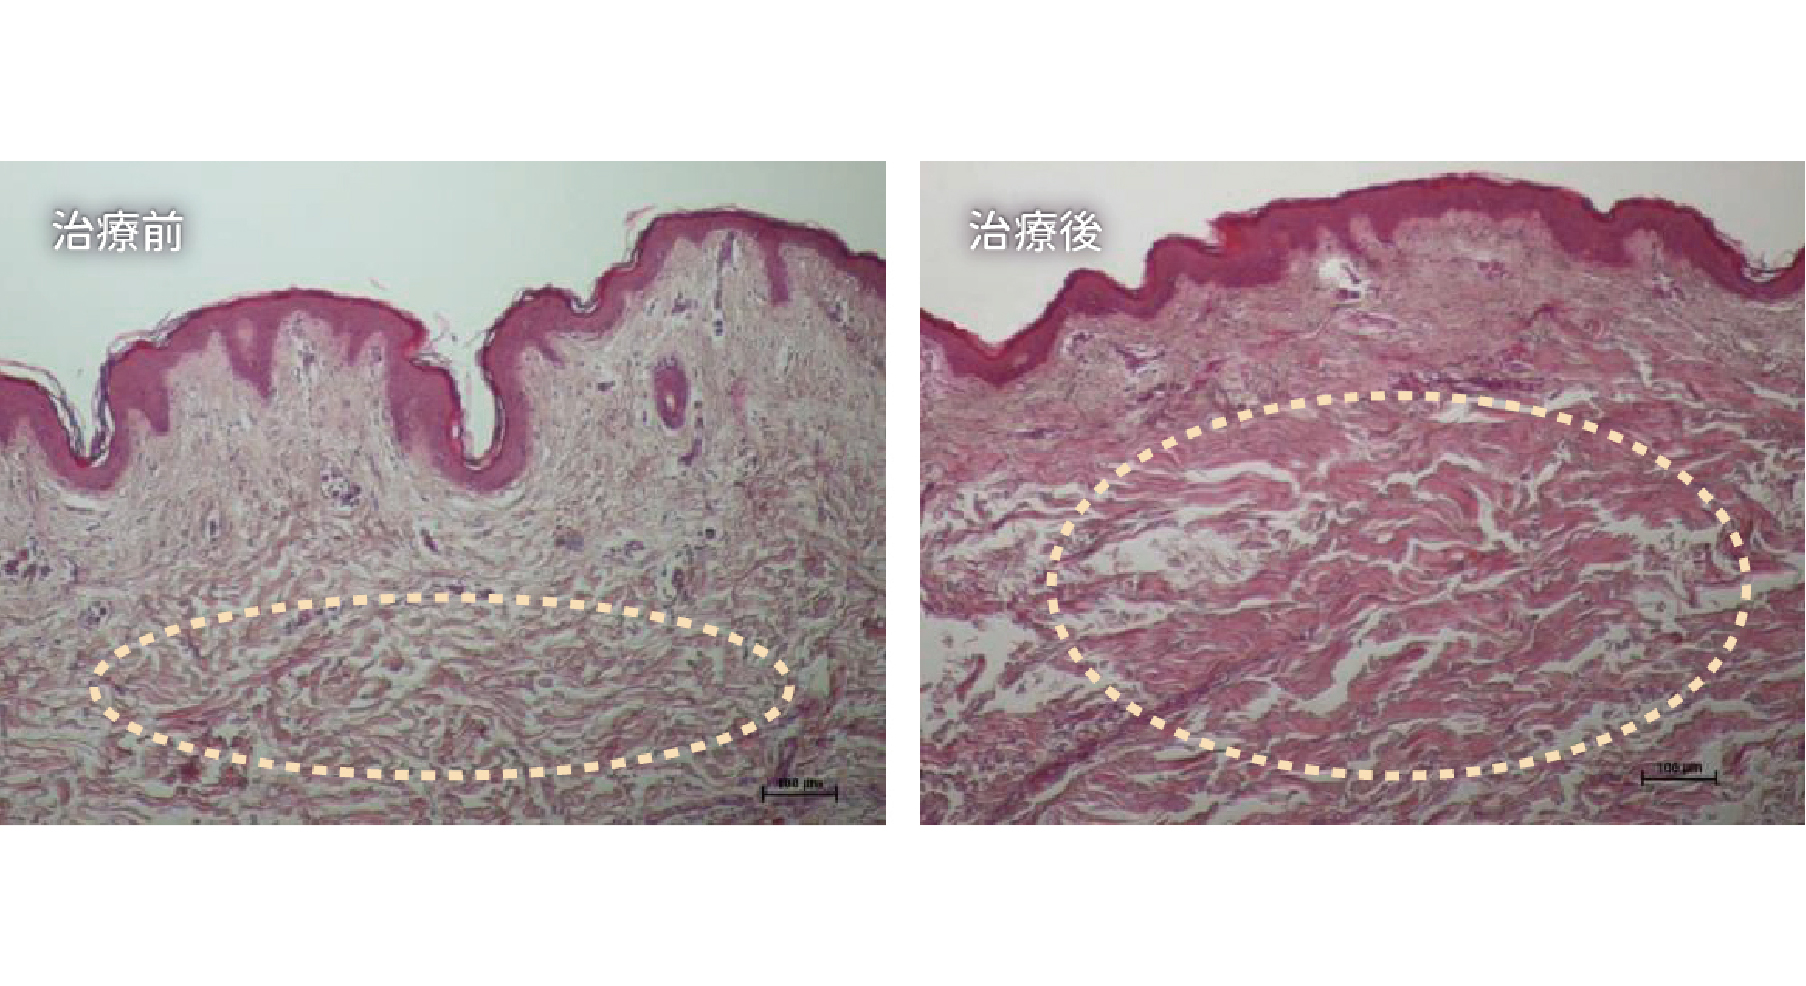

ONDA PRO 臨床研究證明

左圖-治療前

膠原蛋白與彈性纖維結構呈現鬆散、不連續且斷裂

右圖-治療後

膠原蛋白與彈性纖維結構呈現緊密延展,整體密度扎實且均勻分布